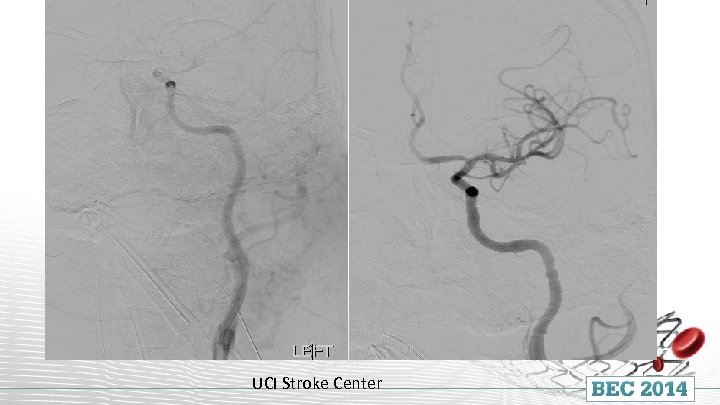

INR suite within 60 minutes of CT completion UCI Stroke Center

Solitaire FR UCI Stroke Center

UCI Stroke Center